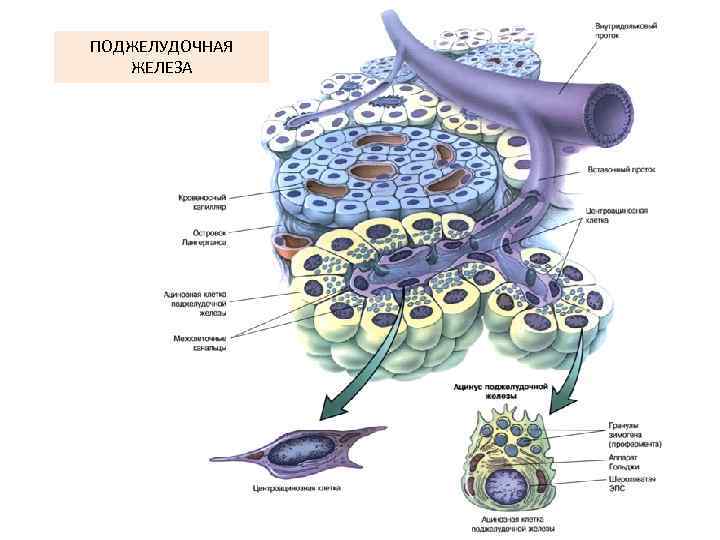

ПОДЖЕЛУДОЧНАЯ ЖЕЛЕЗА

Межацинарный проток

Ацинус и вставочный проток поджелудочной железы

Ациноциты и центроацинозная клетка

Ациноцит поджелудочной железы

Панкреатический островок А клетки – глюкагон В-клетки – инсулин D-клетки – соматостатин D 1 -клетки – вазоактивный интестинальный пептид РР-клетки - панкреатический полипептид

Вставочный и межацинарный протоки поджелудочной железы

Междольковый проток поджелудочной железы (однослойный эпителий)

Зимогенные гранулы